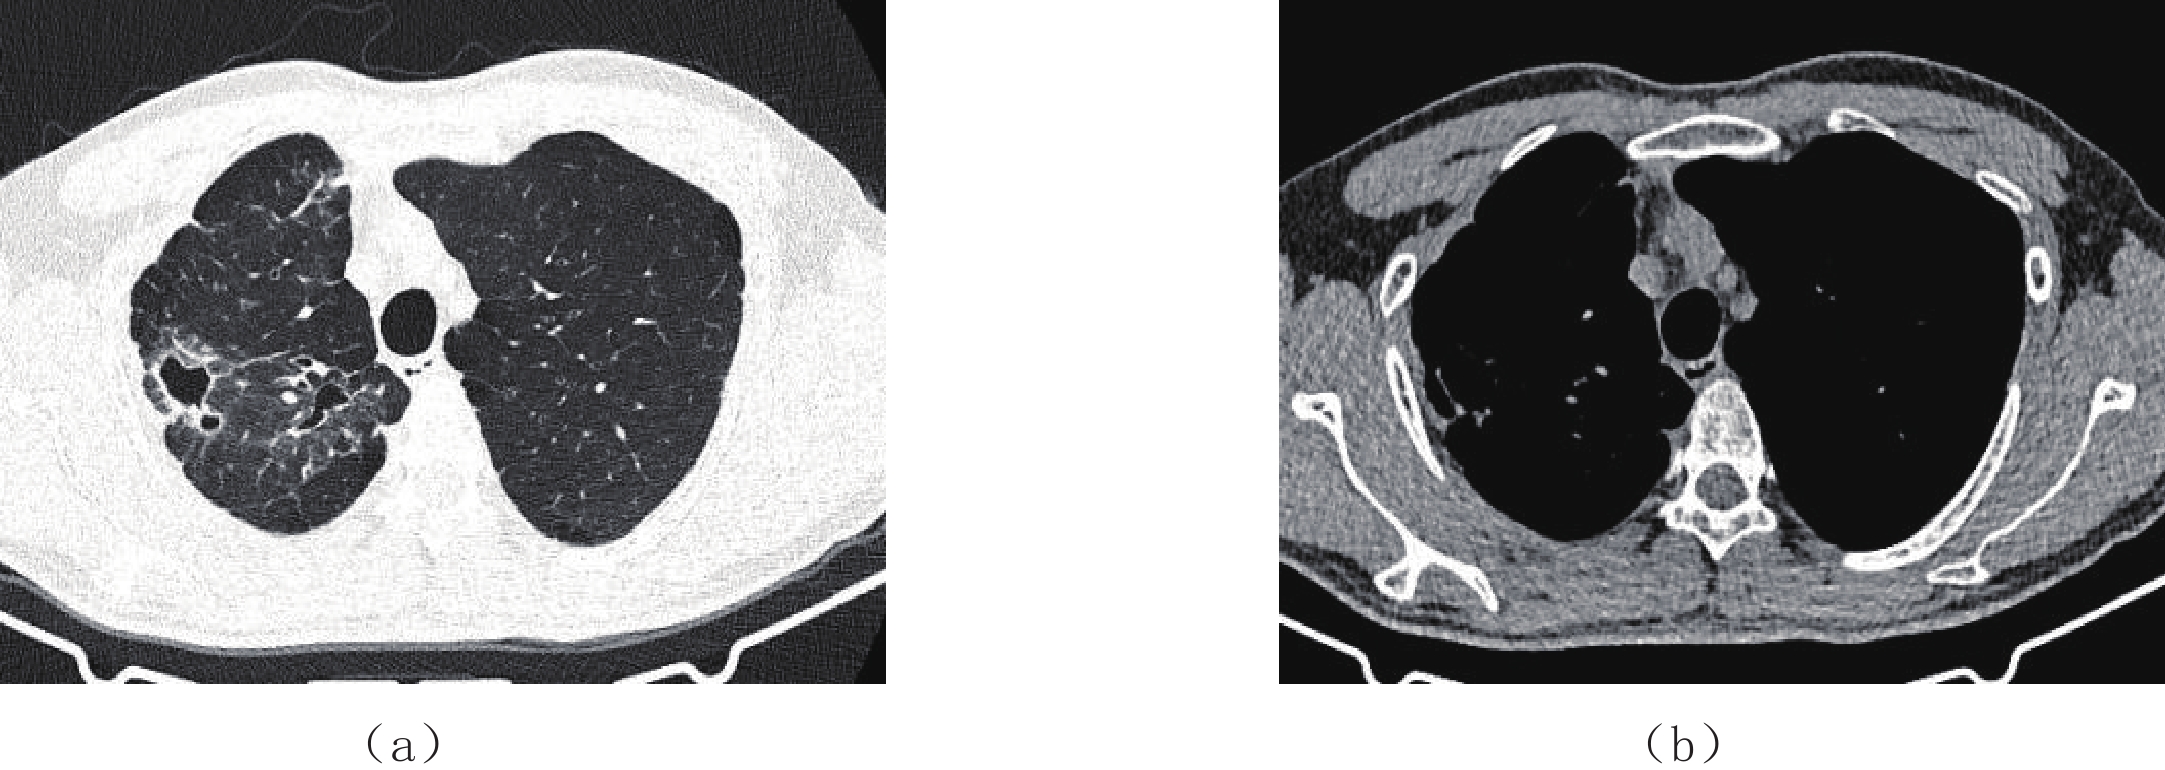

两名放射医师对两组图像主观评价一致性很好。两组图像评分结果≥3分,评分为5分居多,满足临床诊断要求;低剂量组图像主观评分与常规剂量组相比差异无统计学意义(表1、图1和图2)。